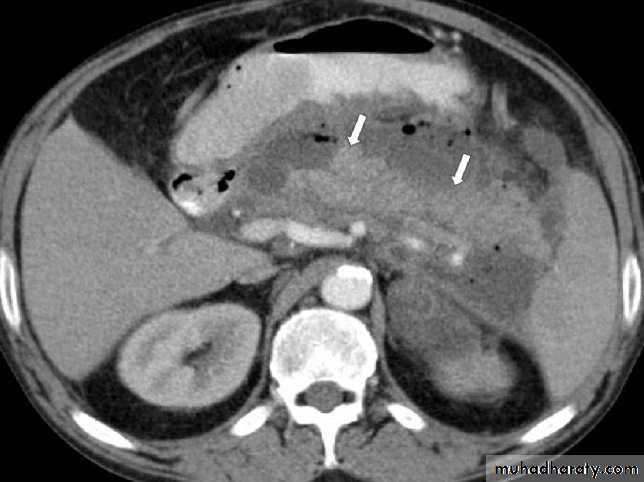

2. CT

- Early:To rule out other causes of acute abdomen

Late (3-8 days):

To define the viability of the pancreas (to detect pancreatic necrosis which manifest as decreased enhancement after iv contrast)

2.Pancreatic necrosis: diffuse or focal area(s) of non-viable pancreatic parenchyma,